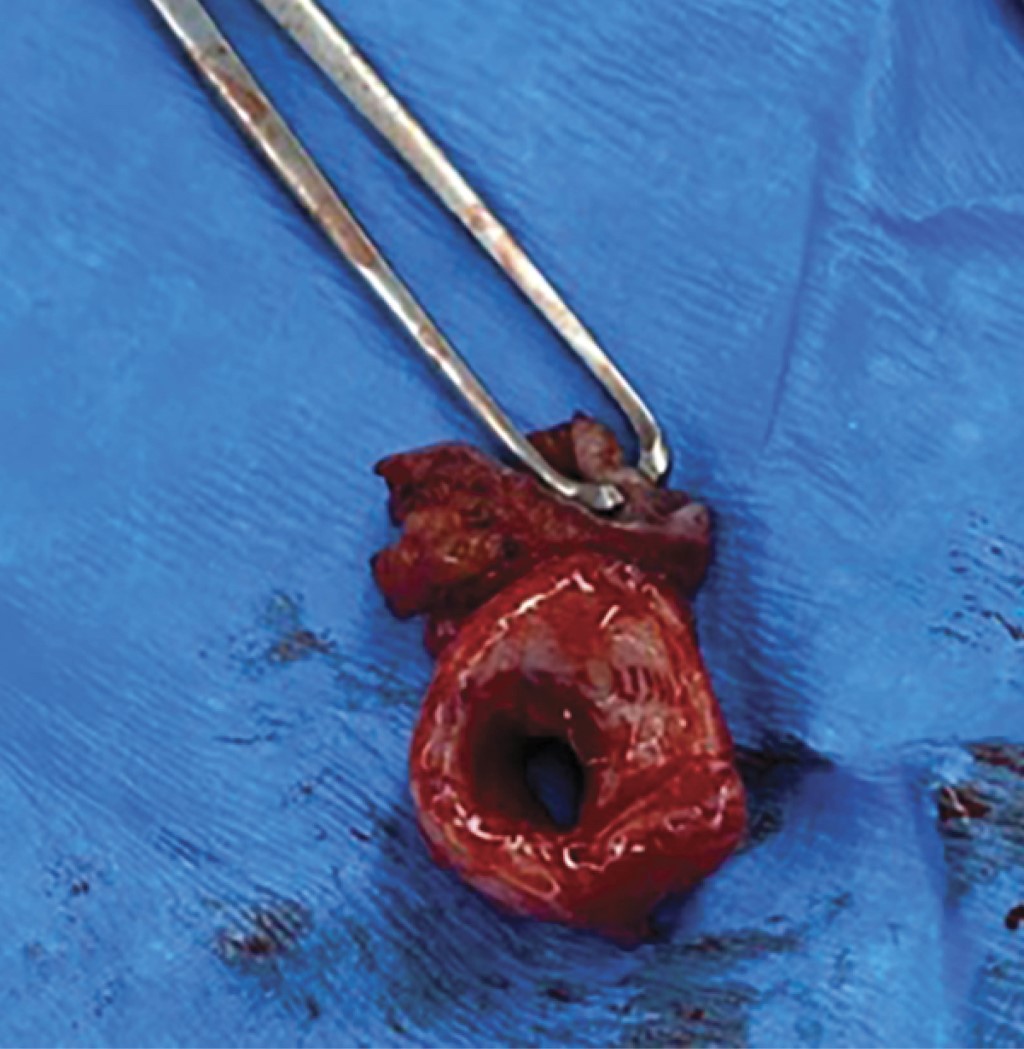

Tracheal resection and anastomosis, continuous versus separated stitches: an experience of 15 years

Acuña-Pinzón, Camilo Levi1,3; Martínez-Zamorano, Monserrat1,4; Acuña-Pinzón, Alan Felipe2,5; Condoy-Nieves, Jefferson Fabián1,6; Narváez-Fernández, Salvador1,7